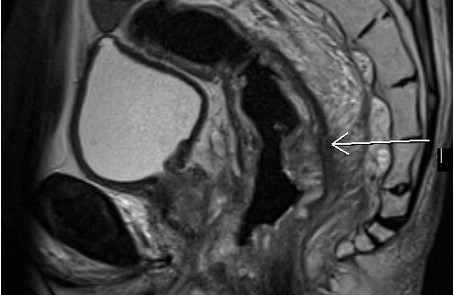

МР исследование прямой кишки и органов малого таза – важный метод исследования, который позволяет визуализировать все отделы прямой кишки, окружающие мягкие ткани, предстательную железу, семенные пузырьки, мочевой пузырь.